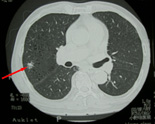

ヘリカルCTにより、3〜5mmの肺がんも発見しています。 肺がんは、CTでなければ、小さいがんは発見しにくいので、 特に、喫煙者には必ずCT検査を勧めます。 |